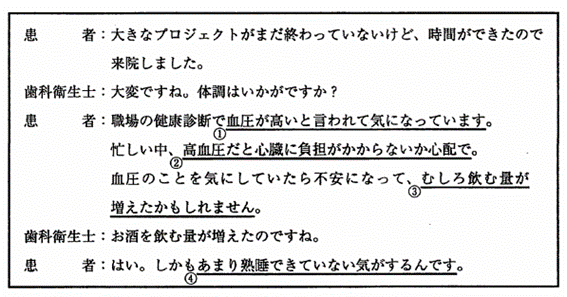

45歳の男性。定期歯科健康診査のため半年ぶりに来院した。最近、ストレスを感じているという。医療面接時の会話の一部を図に示す。ストレスの行動的反応はどれか。1つ選べ。

a. ①

b. ②

c. ③

d. ④

解答を見る

c